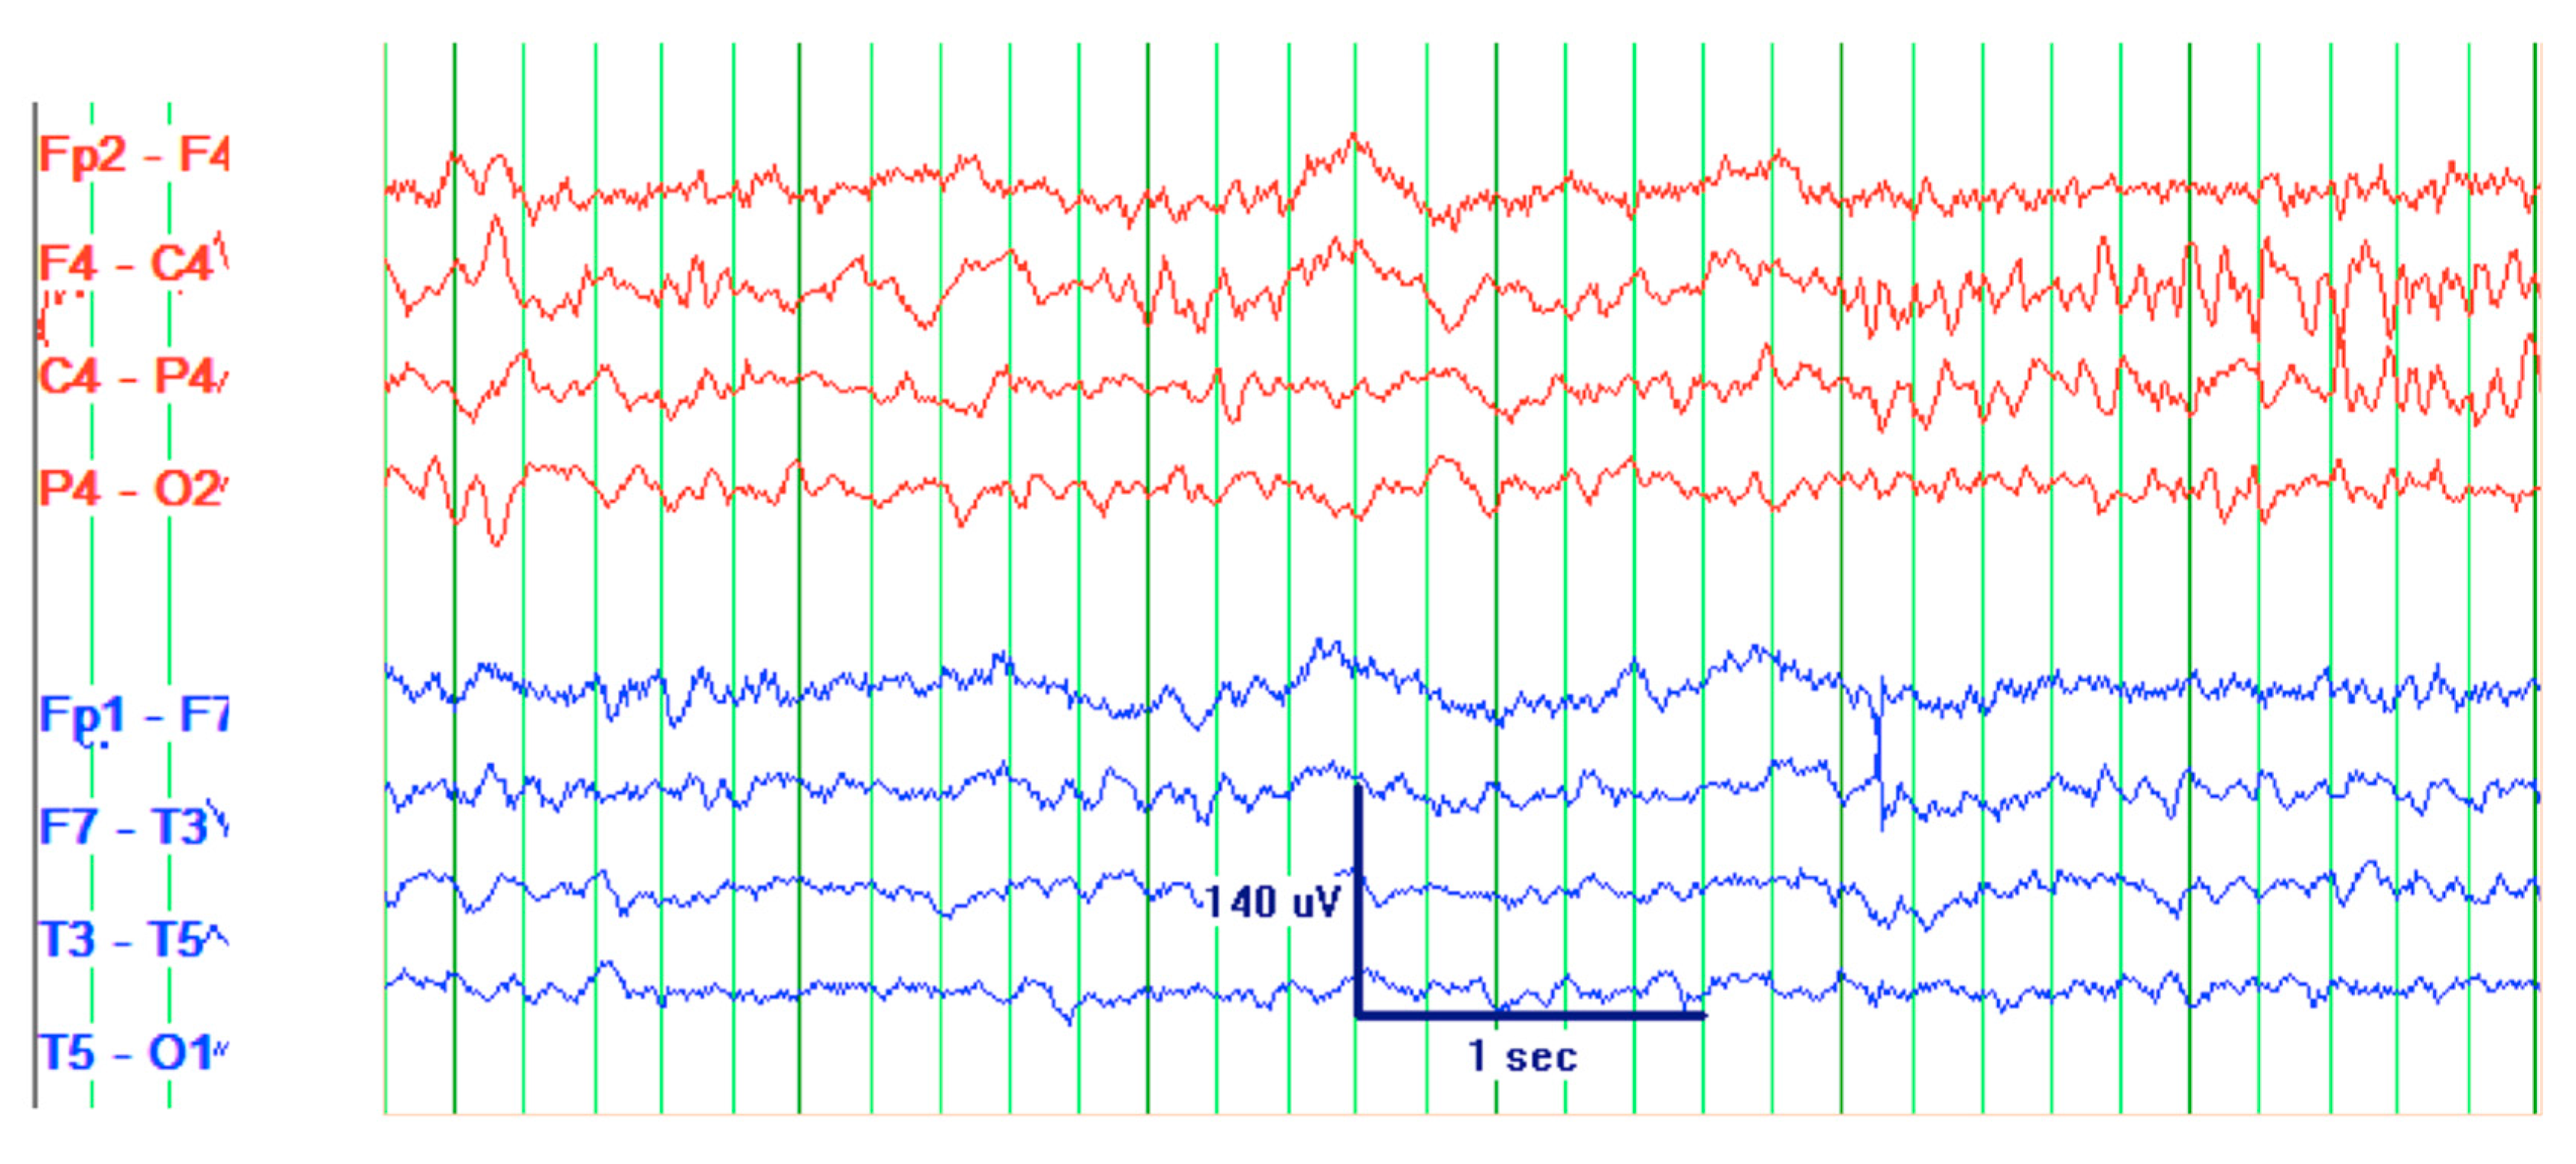

CT scan of the head was reassuring, showing no significant changes from the patient’s previous MRI, performed one month prior to this hospitalization. Unchanged lesions include: small inferolateral left temporal density, associated white matter low density, small medial right and left parietal occipital low densities, and a posterior cerebral white matter hypodensity (Figure 1). Patient’s EEG result read: abnormal EEG due to mild to moderate diffuse slowing, with excess low-moderate voltage polymorphic delta and theta activity (Figure 2).

Figure 2. Electroencephalogram (EEG) of a 61-year-old male with SCNS-DLBCL presenting with acute encephalitis. Consistent with an abnormal EEG reading due to mild-moderate diffuse slowing. This specific frame shows excess low to moderate voltage (15 to 40 uV) polymorphic delta and theta activity. Interpretation of this EEG suggests mild to moderate diffuse cerebral dysfunction. Technical information: Electrodes were placed according to the 10–20 International Electrode System. Digital EEG was recorded using the Natus Digital EEG System and EEG was reformatted into multiple montages as needed.